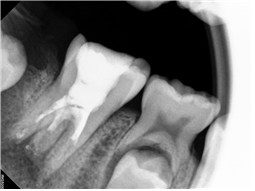

이미지

뿌리 끝에 있던 염증은 말끔히 사라지고, 뼈가 차고 있습니다.

증상도 없고, 보철치료를 하기로 결정하였습니다.